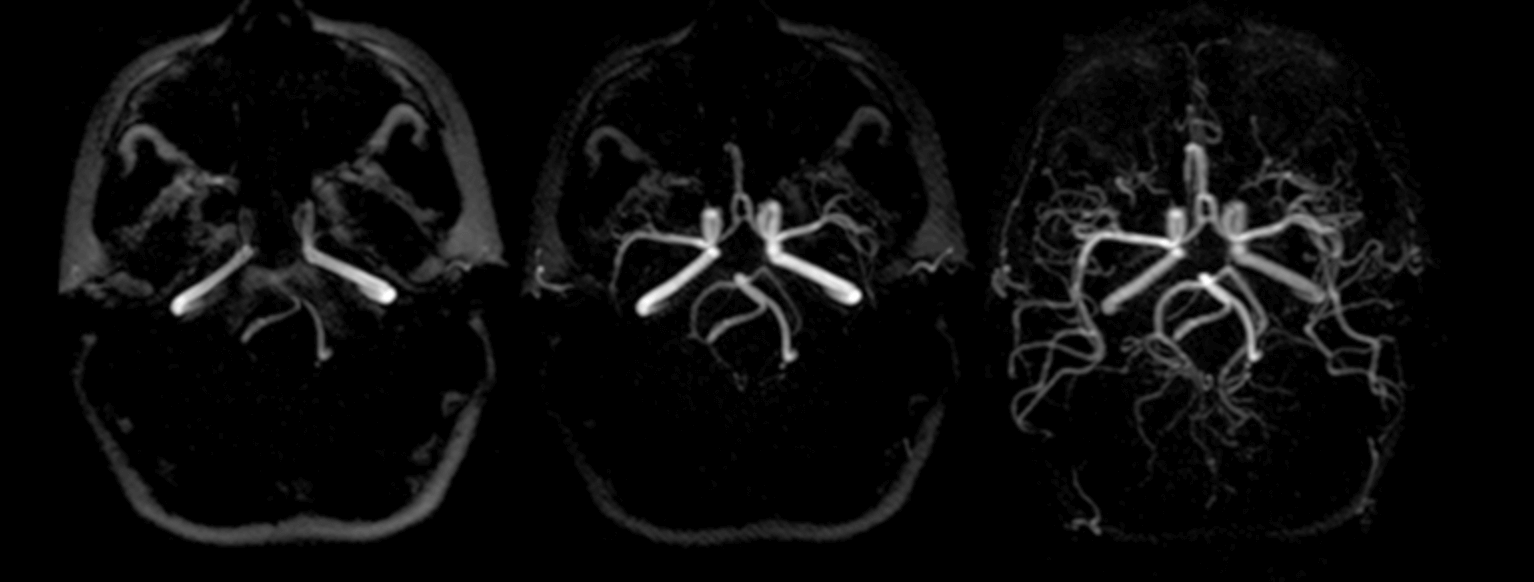

위 두가지 방법의 차이점은 사진을 한번보면 대략 어떤 차이가 있는지 한번에 알수 있습니다. 아래 사진을 보시고 어떤 차이가 있는 지 확인해 보세요.

▣ MRI MRA 사진

뇌MRI를 보시면 종양과 같은 것은 쉽게 찾을수 있을것 이고, 뇌MRA를 보시면 혈류를 볼수 있습니다. 즉 MRA는 혈관에 문제가 생긴것은 보다 쉽게 찾아낼수 있는 검사 입니다.